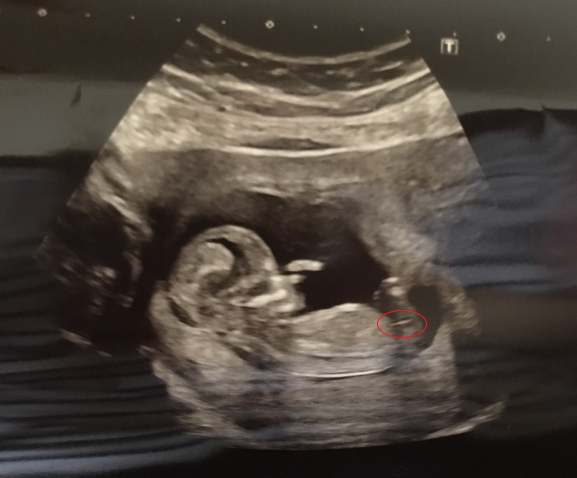

@Tefiti2 what a cracking scan picture!

totally missed your post! @Tefiti2 !! Oh my beuatiful scan pic!

Also i have attached your image with a ring around what i think might be the nub? - I am no expect though btw! If that is a nub looks like a girl?

*oh my what a beautiful scan pic! (that was meant to read!)

Oh that’s great @whisky2014 how are you feeling now? Have you had your 12wk scan yet? Thanks @twittlebee I thought the same, it’s just for fun, can’t believe it’s feeling all a bit more real now! Xx